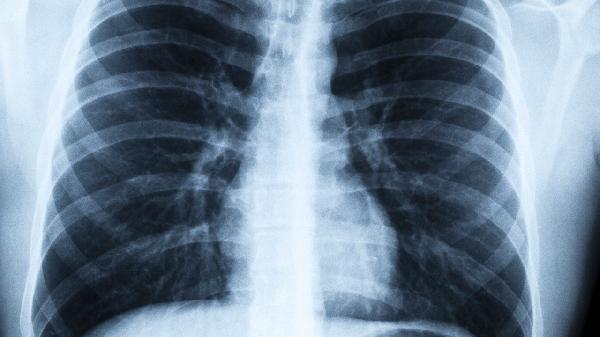

最近不少朋友发现,明明抗原已经转阴,咳嗽却像“狗皮膏药”一样甩不掉。更让人担心的是,有些人的CT报告上悄悄出现了“磨玻璃影”——这种被称为沉默性肺炎的情况,正成为康复路上的隐形地雷。

康复不是百米冲刺,而是需要耐心的马拉松。给身体足够的修复时间,避免过早进行剧烈运动或过度劳累。如果出现上述危险信号,务必及时到呼吸科进行肺部CT检查。记住,对待身体要像对待刚发芽的幼苗——温柔呵护才能茁壮成长。